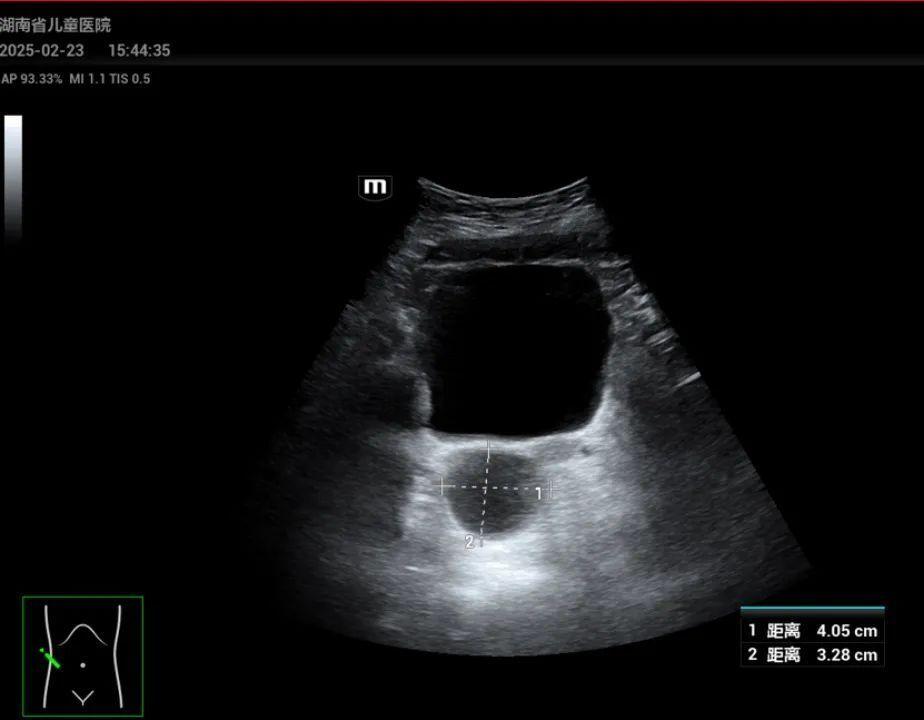

最近,陈女士将孩子带到湖南省儿童医院肝病内分泌科就诊,经过副主任医师谭艳芳体查发现,晗晗乳房已有发育变大迹象,B超报告显示“盆腔偏右侧囊性包块,左侧卵巢可见多个直径大于4mm的卵泡,双侧乳房可见腺体回声”。谭艳芳告诉陈女士,孩子是外周性性早熟,可能需要手术治疗。

值得注意的是,4例患儿盆腔B超均提示存在囊性包块。谭艳芳表示,当女孩单纯出现阴道出血时,要注意排除阴道感染、异物或肿瘤等,需进一步排查病因。